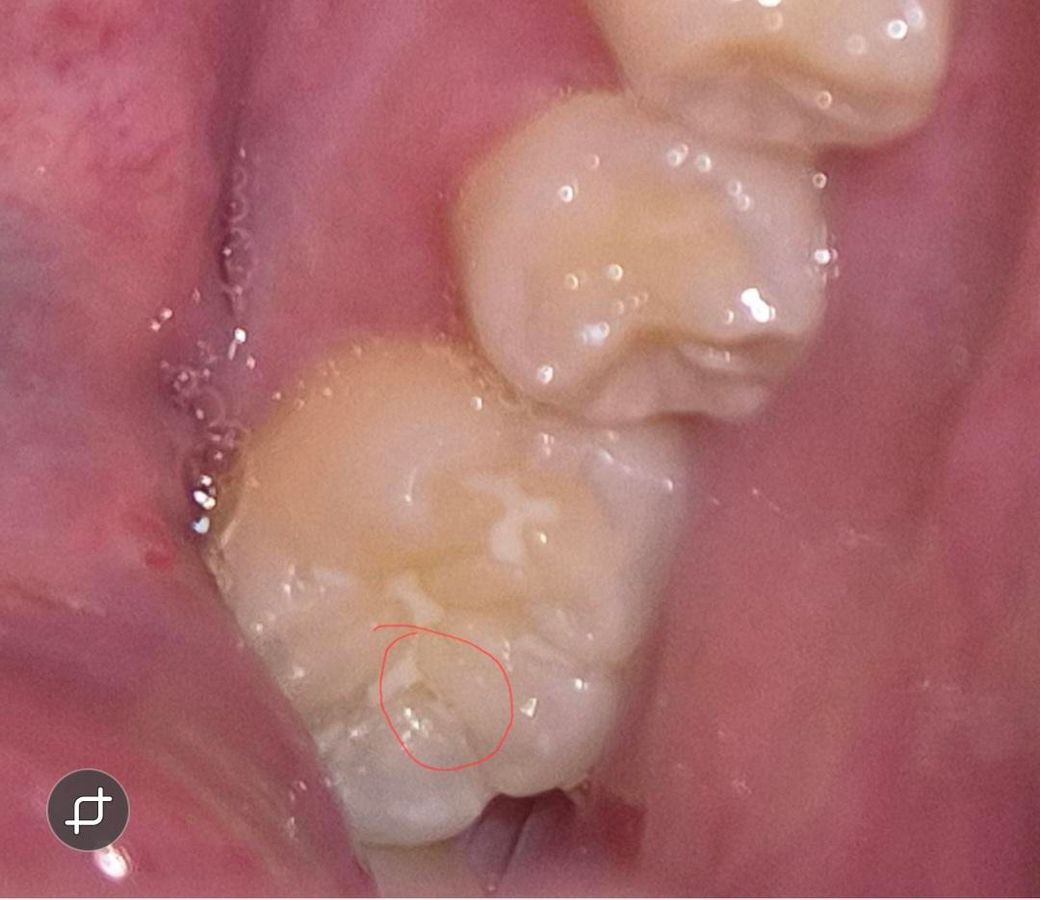

아이 어금니 실란트 떨어진 부위? 충치인건지요

어금니 동그라미친 부분인데요 , 실란트가 부분부분 삭제되긴했어요 근데 유독 저부분만 뒤쪽이긴하지만 각도때문인건지 신경쓰여서요 치과에서는 충치는아니고 실란트가 떨어져서 그렇고 빛에따라서 음영? 암튼 눈으로보면 뭐가껴있거나 그런식으로 색이 보여질수는있다고, 치과빛으로비춰 거울로보고 검진해도 충치는아니라고하셨는데 .. 왤케신경이 쓰이는건지.. 제가 어떤각도에서보면 유독저부분이 진짜뭐가껴있거나 충치같은색으로 보이기도하고 또어떤각도에선 괜차나보이기도하고 그러긴해요 ㅜㅜ 다른전문가분들의 의견이궁금합니다

충치는 아닌거 같고 저 사이에 음식물이 꼇거나 어둡게 보여서 그러는거 같으니 걱정하지 않으셔도 될것같습니다.

충치는 아니고 골짜기의 그림자 같습니다 다만 저렇게 실란트가 떨어지고 틈이 있는채로 두면 충치가 잘생깁니다 보완을 해주면 좋을 것 같습니다